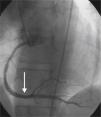

A 64-year-old white woman with a history of hypertension was admitted to hospital with new-onset chest pain consistent with angina. She had had multiple coronary angiograms (CA) four years previously for repeated episodes of typical chest pain and admissions. The CA showed non-obstructive coronary artery disease in the range of 40–50% in the left circumflex artery (LCx) which was confirmed to be non-obstructive by fractional flow reserve during the angiogram; no catheter-induced vasospasm occurred during the CA. Because of continued episodes of chest pain, she was taken off metoprolol and started on diltiazem 240mg once a day for possible vasospastic angina. She was then asymptomatic for the following four years, and also had a dobutamine stress echocardiogram, which was negative, about two months before the present admission for screening due to disease identified on her last CA. At this admission, she had new symmetrical anterolateral and inferior T inversion on the ECG consistent with ischemia; troponin levels were minimally elevated (0.3ng/ml). The patient had been seen by her primary care physician three days previously for a routine follow-up and was taken off diltiazem and started on nebivolol 10mg/day in addition to her medications of HCTZ 25mg and lisinopril 40mg/day, Lipitor 40mg, and enteric-coated aspirin 325mg/day for blood pressure (BP) control. In hospital she was started on nitro paste and intravenous (IV) heparin and her home medications continued. Because of continued chest pain in hospital and mildly elevated troponin I levels, she was scheduled for CA. She experienced chest pain at the beginning of the coronary angiogram, which initially revealed a 70% lesion and slow flow in the mid left anterior descending artery (LAD), a 90% lesion in the mid LCx and a 99% lesion in the ostium of the second obtuse marginal (OM2) (Figure 1, black arrow). The right coronary artery (RCA) had a distal 80–90% stenosis (Figure 2, black arrow). During preparation for percutaneous intervention in the LCx and OM2, intracoronary (IC) nitroglycerin was given for vessel sizing, after which there was resolution of the lesions in the LAD and decrease in the mid left LCx lesion to 50–60%, and resolution of the OM2 lesion, suggestive of significant reversible coronary artery spasm (Figures 3 and 4, white arrows). IC nitroglycerin was also administered in the RCA, in which lesion resolution was also seen. The coronary intervention was aborted, the patient's chest pain was resolved after IC nitroglycerin and she was started on IV nitroglycerin in the interim. Nebivolol was discontinued; diltiazem started in post-catheterization orders. She continued to have occasional episodes of chest pain for about 24hours after discontinuation of nebivolol. She was weaned from IV nitroglycerin the next day and started on oral isosorbide mononitrate. The following day the ECG changes resolved with no more episodes of chest pain; she was discharged home and was event-free in follow-up.